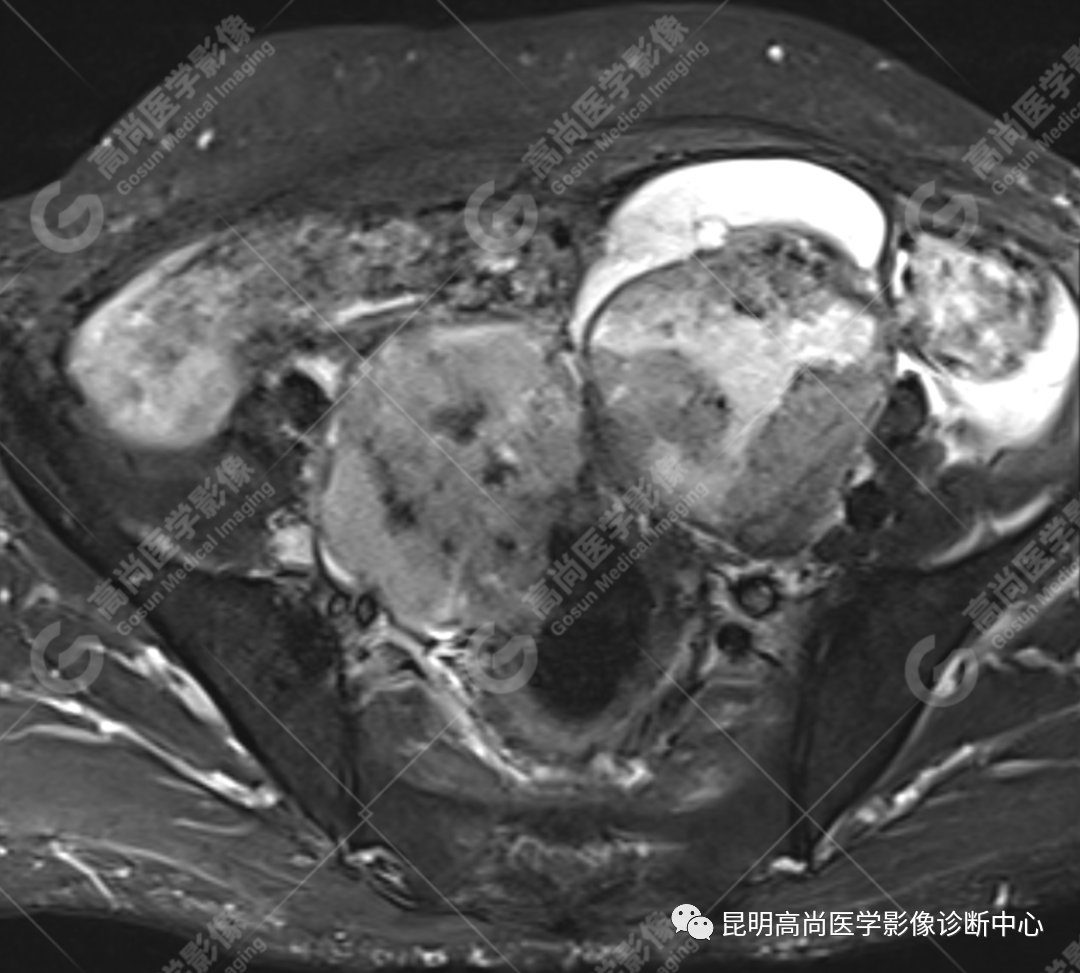

影像诊断

子宫、附件未见显示;下腹部及盆腔内巨大占位,考虑恶性肿瘤,肉瘤可能,阴道及肛管受侵,建议活检。

MRI 表现

不规则菜花状或息肉状肿物,子宫内膜正常 T2WI 清晰连续的高信号消失,取而代之是中高、高信号,不均匀混杂信号,信号强度低于内膜正常信号强度,T1WI 上内膜信号增高,子宫肌层明显变薄,未受侵者肌层信号均匀,因肿物组织来源不同,病变信号复杂,以 T2WI 表现为等高混杂信号为主。因病灶较大,可合并囊变坏死及肿瘤出血。

肌层到肿块内的血管流空信号,可提示肿瘤内有血供丰富的肉瘤成分,血管流空信号在子宫内膜癌中未见报道,但在子宫平滑肌瘤、平滑肌肉瘤中可见。